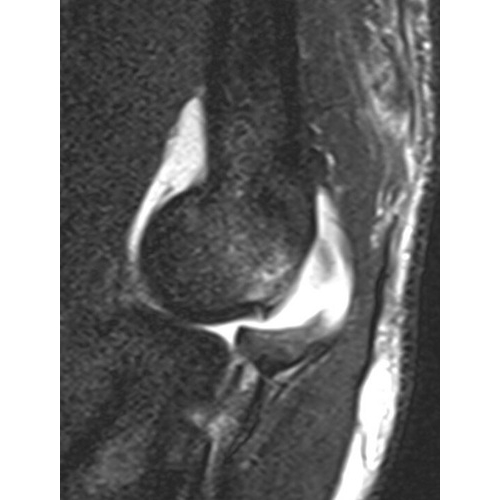

MRI Impression:

1. There is a bony avulsion of the triceps insertion from the olecranon which accounts for the bony fragments seen on preceding radiographs. There is retraction of the tendon stump 2.5 cm with surrounding edema.

2. There is a moderate to high-grade ulnar collateral ligament tear involving the distal attachments to the sublime tubercle of the ulna.

3. There is edema from a bone contusion in the coronoid process of the ulna without evidence of displaced fracture at that site. Case Photo #2 and Case Photo #3